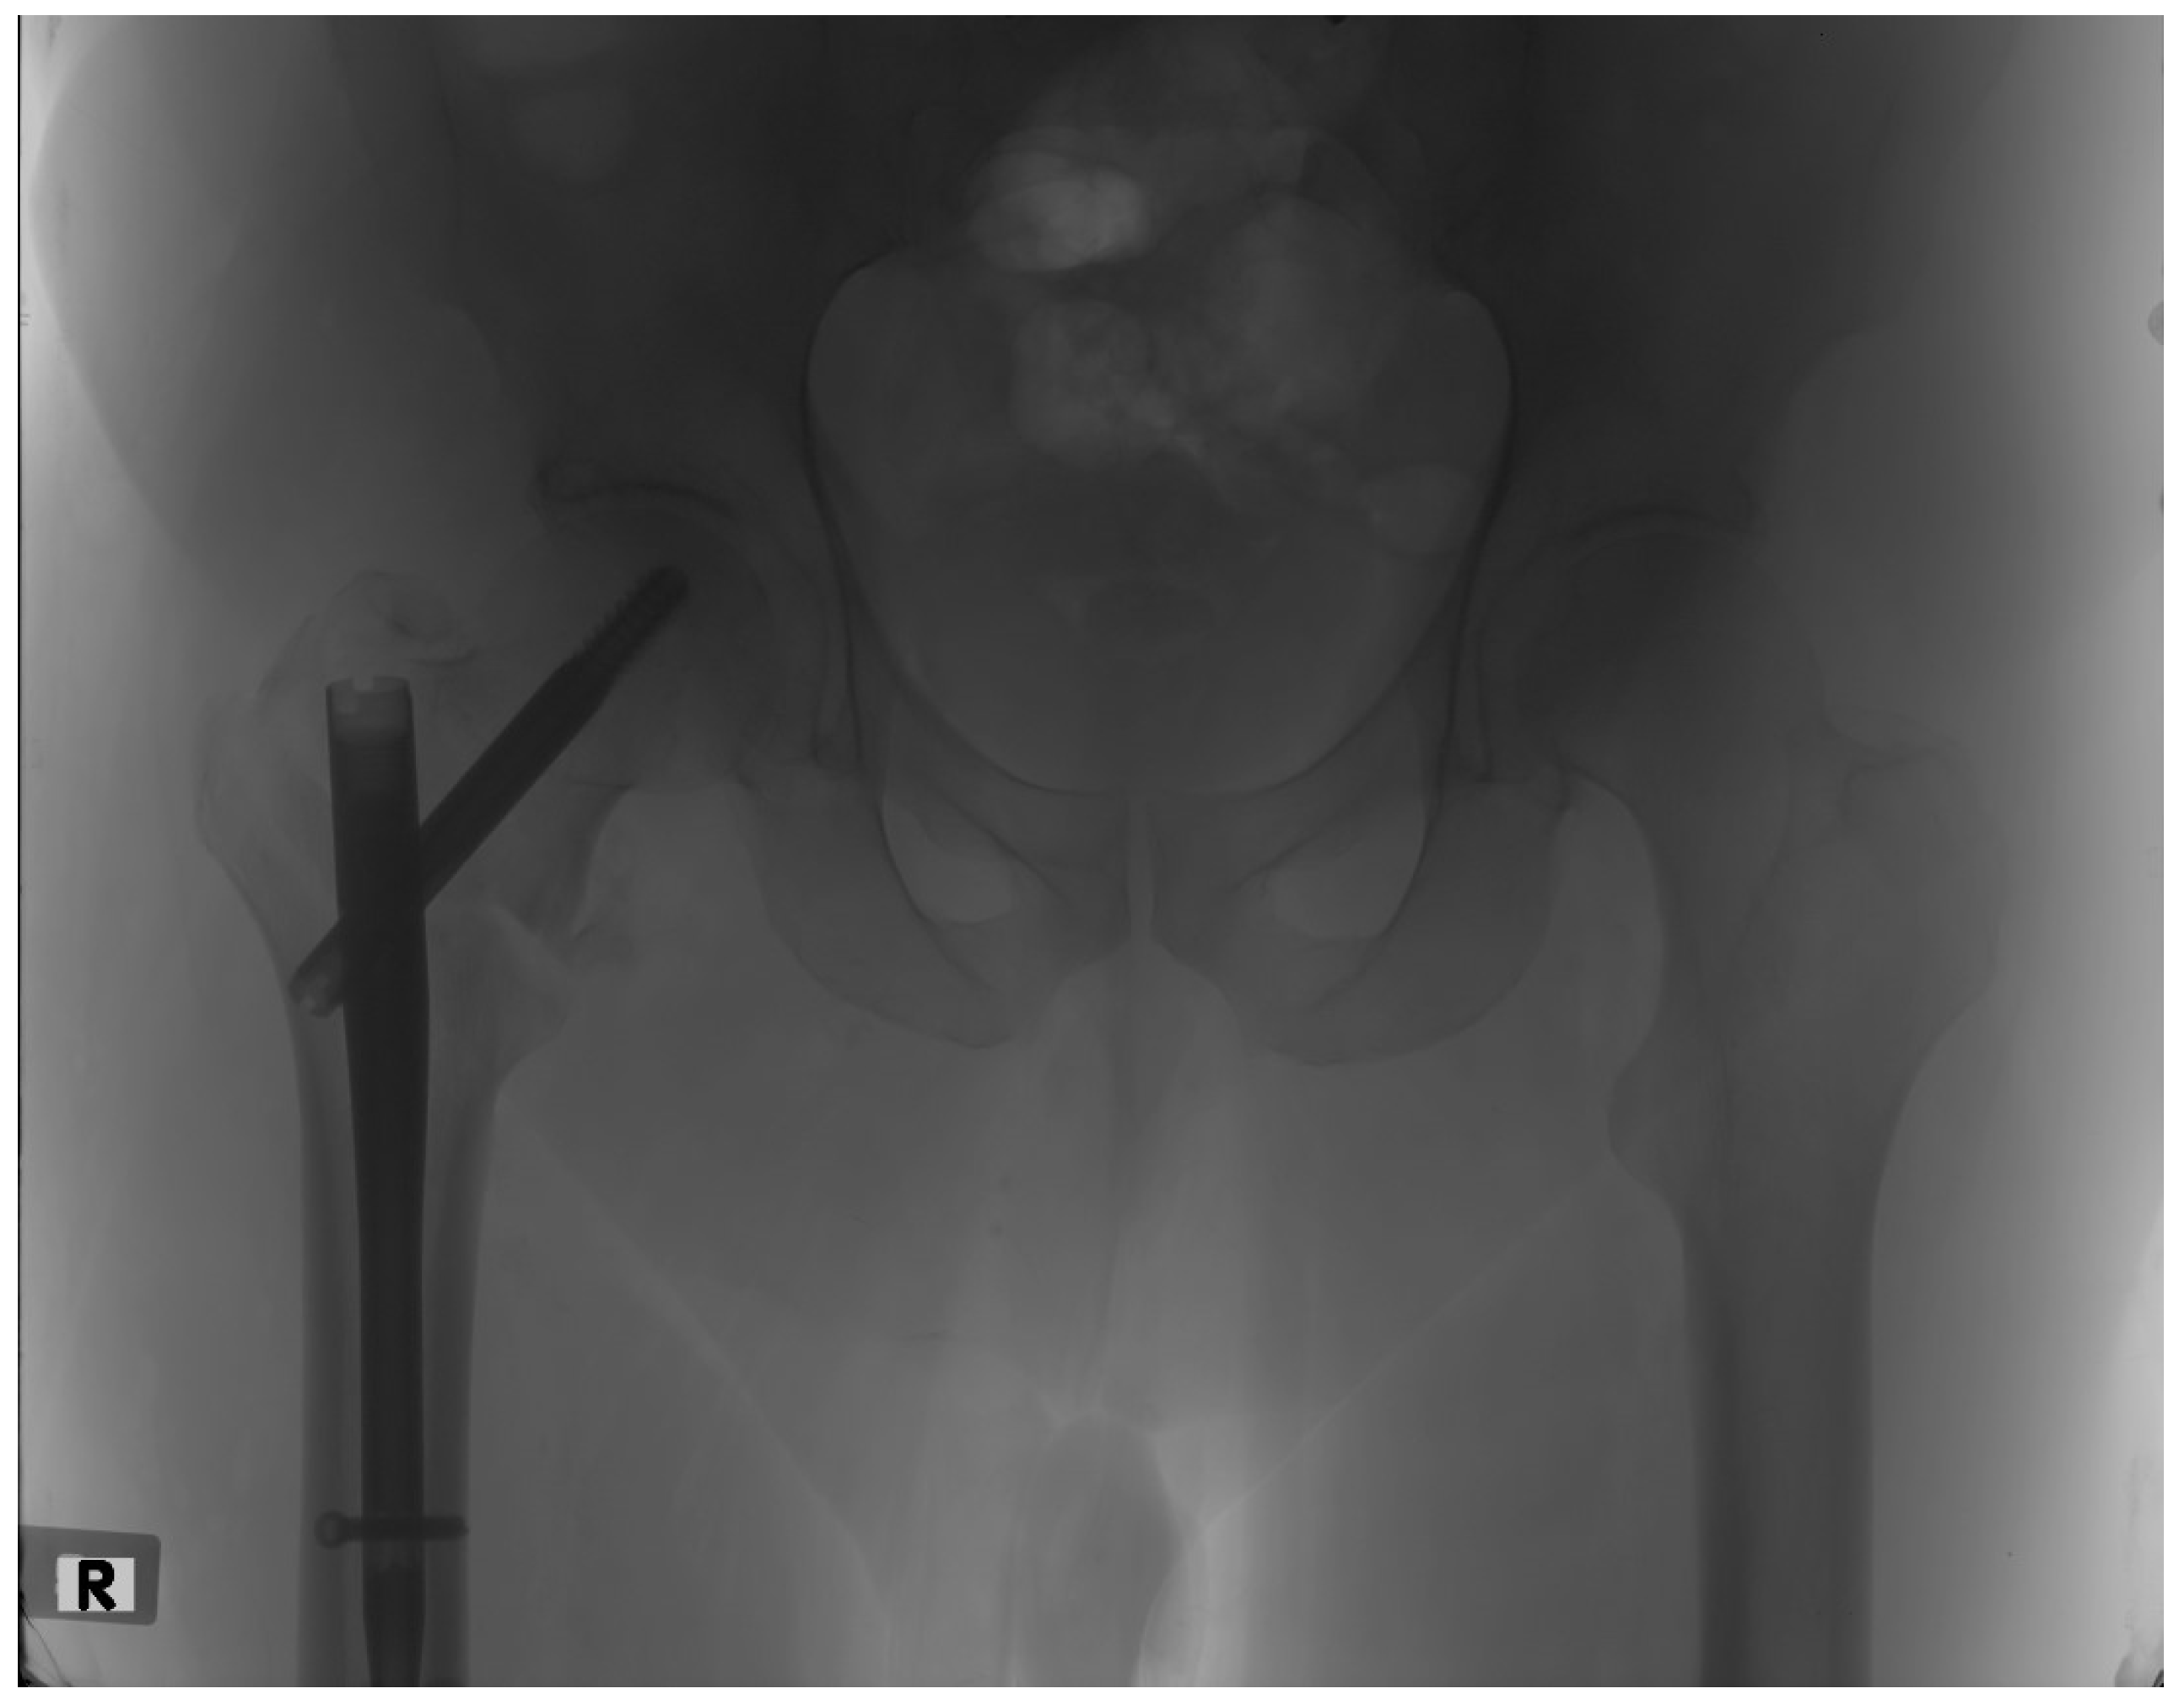

In the current study, only a few patients experienced any postoperative complications. One of the possible complications that was meticulously studied was fracture non-union, as it was thought to be closely associated with rotational alignment, as well as having a significant impact on functional outcome. The evaluation of fracture union was based on radiographic imaging in combination with a clinical examination at the 6-month follow-up. Only two (3%) of our patients presented with a non-union (Figure 3) and were reoperated on. No relationship was found between the postoperative difference in femoral anteversion and fracture union, as the statistical values did not exceed the thresholds of significance (p-value = 0.698).

Figure 3.

Hip X-ray of a patient presenting with an intertrochanteric fracture non-union at the 6-month follow-up.